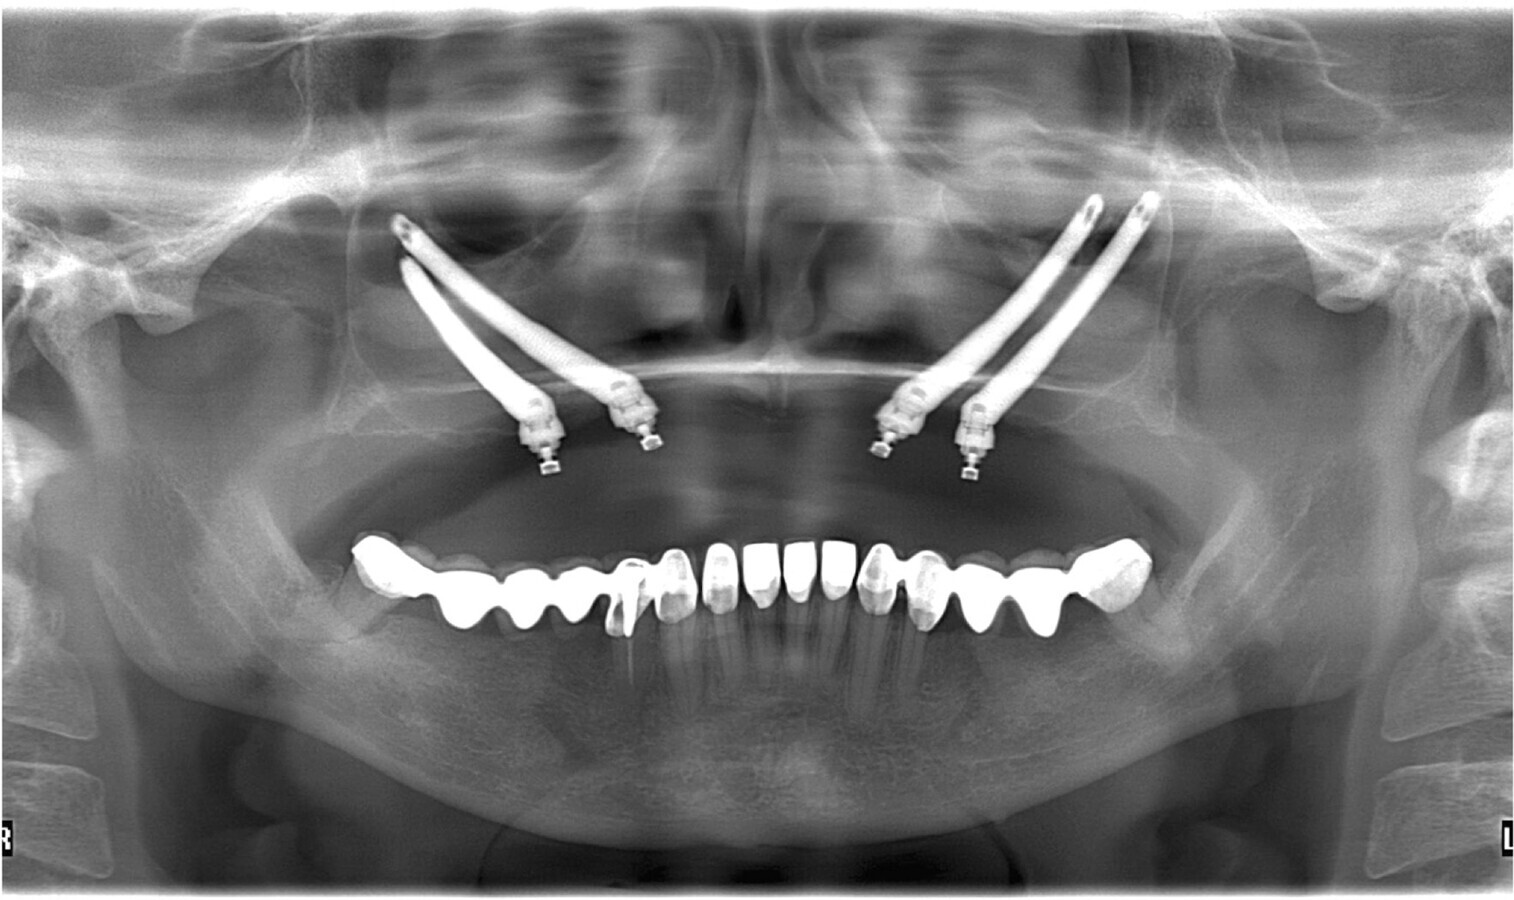

Fig. 7. Radiografía panorámica postoperatoria de Quad Zygoma.

El procedimiento quirúrgico se realiza siguiendo los lineamientos protocolarios para este tipo de cirugía, bajo anestesia general y entubación naso-traqueal. Se colocan los 4 implantes zigomáticos y los pilares protésicos Multi-Units con un torque de 30N/cm210,11. De acuerdo al protocolo establecido para este caso, se dejará un tiempo de 4 meses de oseointegración para luego dar inicio a la rehabilitación del caso por medio de una prótesis fija atornillada a los implantes.

Se realiza una nueva evaluación clínica y radiográfica para determinar el tratamiento en la nueva tomografía dental volumétrica, valorar el hueso a nivel del zigoma, las dimisiones antero-posteriores y mediales laterales del mismo, la topografía de la pared anterior del seno maxilar y la cantidad de hueso alveolar residual de la maxila7,8.